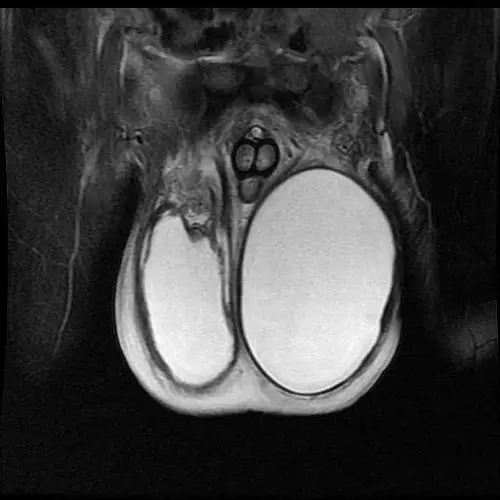

男性睾丸萎缩的表现有哪些